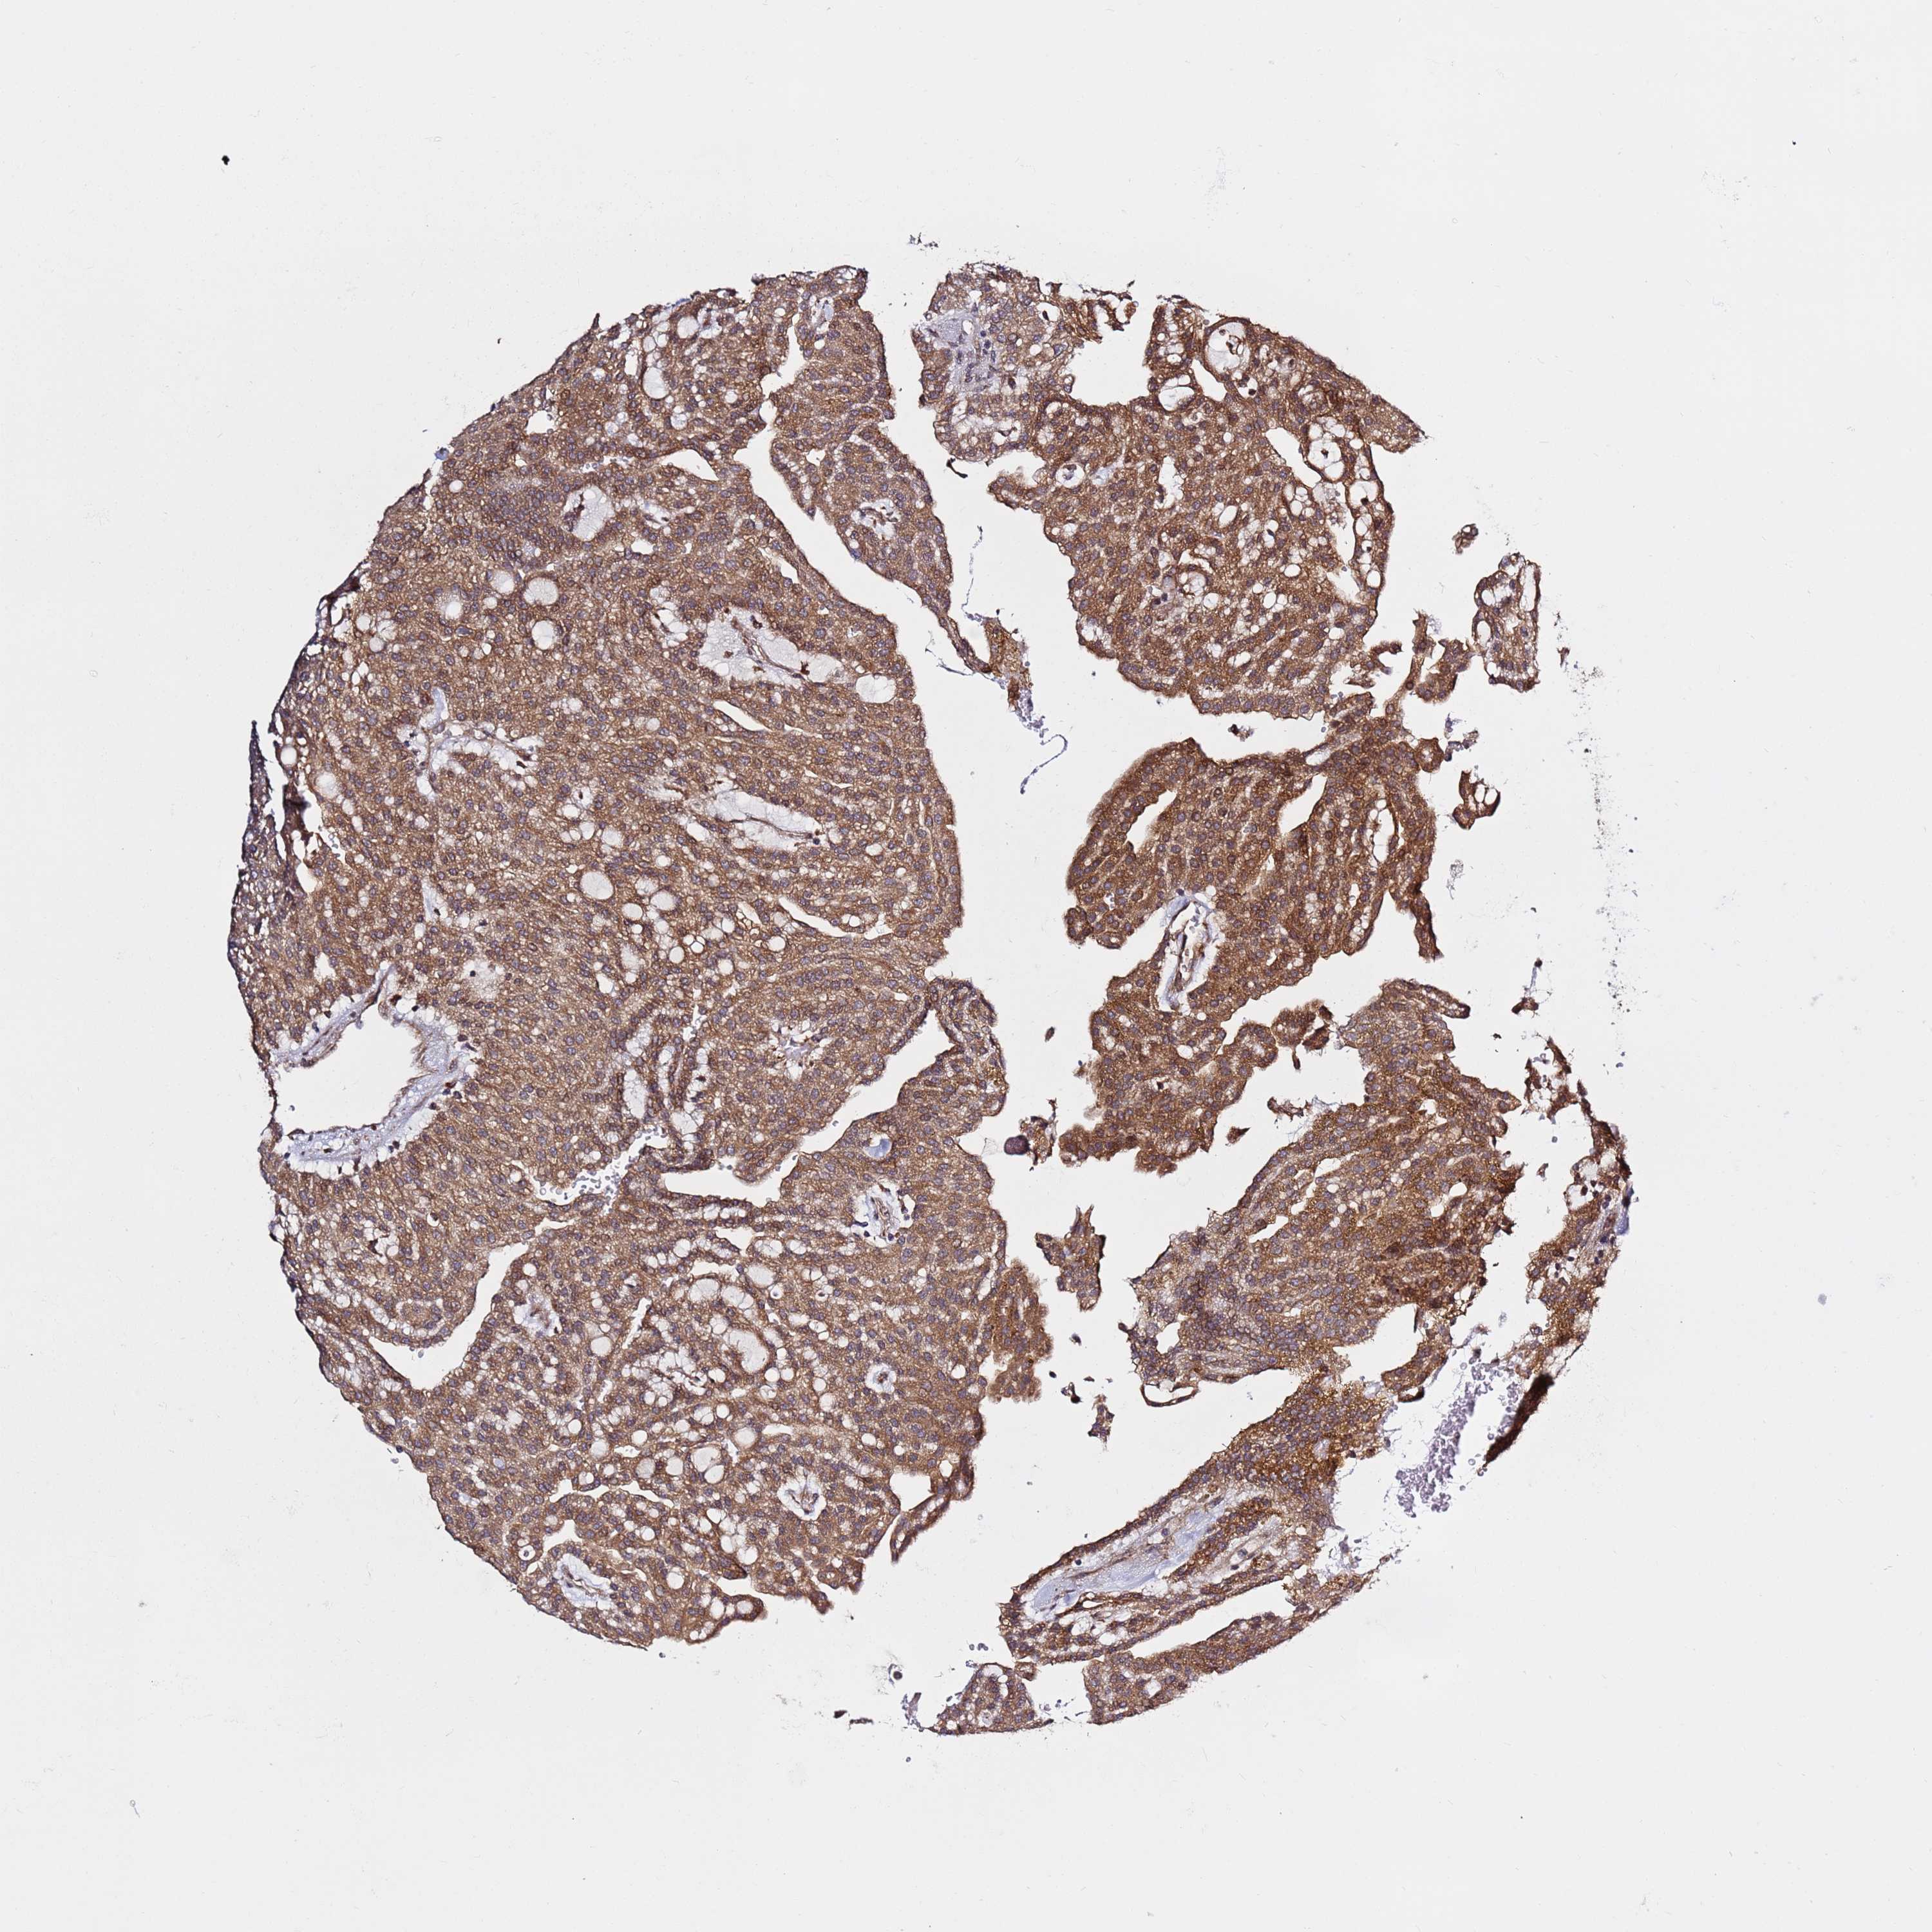

KIDNEY RENAL CLEAR CELL CARCINOMA (VALIDATION) - Interactive survival scatter ploti

The Survival Scatter plot shows the clinical status (i.e. dead or alive) for all individuals in the patient cohort, based on the same data that underlies the corresponding Kaplan-Meier plots. Patients that are alive at last time for follow-up are shown in blue and patients who have died during the study are shown in red.

The x-axis shows the expression levels (FPKM) of the investigated gene in the tumor tissue at the time of diagnosis. The y-axis shows the follow-up time after diagnosis (years). Both axes are complimented with kernel density curves demonstrating the data density over the axes. The top density plot shows the expression levels (FPKM) distribution among dead (red) and alive patients (blue). The right density plot shows the data density of the survived years of dead patients with high and low expression levels respectively, stratified using the cutoff indicated by the vertical dashed line through the Survival Scatter plot. This cutoff is automatically defined based on the FPKM cutoff that minimizes the p-score. The cutoff can be changed by dragging the vertical line or by entering a cutoff value in the square labeled "Current cut-off".

Under the Survival Scatter plot the p-score landscape (black curve; left axis) is shown together with dead median separation (red curve; right axis). Dead median separation is the difference in median mRNA expression between patients who have died with high and low expression, respectively. It is calculated as follows: median FPKM expression of dead patients with high expression - median FPKM expression of dead patients with low expression. This is intended to aid the user in visually exploring custom cutoffs and the associated p-scores and dead median separation.

Individual patient data is displayed and can be filtered by clicking on one or more of the category buttons on the top of the page. Categories describing expression level and patient information include: high, low, alive, dead, female, male and tumor stages. The scale of the x-axis can be toggled between linear and log-scale by clicking on the "x log" button. Mouse-over function shows TCGA ID, patient information and mRNA expression (FPKM) for each patient.

& Survival analysisi

Kaplan-Meier plots summarize results from analysis of correlation between mRNA expression level and patient survival. Patients were divided based on level of expression into one of the two groups "low" (under cut off) or "high" (over cut off). X-axis shows time for survival (years) and y-axis shows the probability of survival, where 1.0 corresponds to 100 percent.

PRKAB2 is potential prognostic, high expression is favorable in Kidney Renal Clear Cell Carcinoma (validation)

Best expression cut offi

Based on the FPKM value of each gene, patients were classified into two groups and association between prognosis (survival) and gene expression (FPKM) was examined. The best expression cut-off refers the FPKM value that yields maximal difference with regard to survival between the two groups at the lowest log-rank P-value. Best expression cut-off was selected based on survival analysis .

When clicking on this number, the vertical dashed line indicating cut-off, the interactive survival plot, and the Kaplan-Meier curve will be adjusted to show results based on the best expression cut-off.

: 8.55

TCGA RNA samplesi

RNA-seq data is reported as average FPKM (number Fragments Per Kilobase of exon per Million reads), generated by the The Cancer Genome Atlas (TCGA) .

Normal distribution across the dataset is visualized with box plots, shown as median and 25th and 75th percentiles. Points are displayed as outliers if they are above or below 1.5 times the interquartile range. FPKM values of the individual samples are presented next to the box plot.

Average pTPM 10.2

Number of samples 100